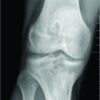

Six weeks following surgery follow up radiographs showed good bone healing in an anatomic position and she achieved full range of motion in both shoulders, totally free from pain. At eight weeks, follow up radiograph showed a complete fracture healing of both clavicles. Subsequently patient was mobilized under full load.

Bilateral clavicular fractures have been treated well with plates and screws [16], external fixation methods [10] and combination of conservative on one side and intramedullary fixation on other side [20] but we did not come across any literature support for concurrent bilateral traumatic fracture of clavicle treated with intramedullary K wire though one case report suggested idiopathic concurrent nontraumatic bilateral fracture of clavicle should be considered for differential diagnosis of fracture clavicle [21].Our aim was to check out the feasibility and functional outcome in terms of pain ,range of motion and union of fracture after surgical management of concurrent bilateral traumatic fracture of clavicle with intramedullary fixation in single sitting. Strauss et al [22] had shown similar results in a series of 16 patients of unilateral fracture clavicle treated with intramedullary fixation. The advantages of using intramedullary fixation are minimally invasive, safe alternative to plate and screw fixation, intramedullary compression, minimal stripping of periosteum, cosmesis and rapid recovery as outlined by Khalil [23] and Mueller et al [24]. The reasons for primary surgical stabilization in our case are completely displaced bilateral fractures and marked risk of non union or poor result in female patients as suggested by Smekal et al [25],Duijff et al [26] and Pieske et al [27]. Braunstein et al [20] revealed that quick analgesia and high mobility can be easily achieved in bilateral clavicular fractures if treated with intramedullary fixation which is in accordance with our report. A handful of case series or case reports showing age, sex, mode of injury with modality of treatment with complications encountered are tabulated below [Table 1] which concludes that majority of bilateral involvement occurred in females because of high velocity trauma and in all except two studies [14,15] (fracture treated non operatively in both) there was no complication which is similar to our study. We were not able to find out any published recommendation concerning conservative or operative treatment for displaced bilateral traumatic clavicular fractures .The patient presented here, showed good clinical outcome concerning pain, function and union of fracture [Fig. 1] although the intramedullay K wire used was not strong enough, hence the arms could not be mobilised under complete load reduction.